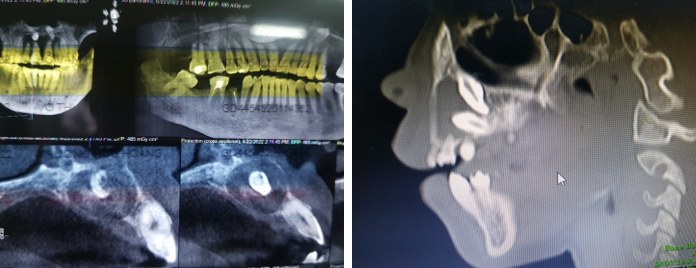

Hình ảnh nang thân răng do 2 răng thừa (mesiodent) ngầm trên CT Cone Beam và nang thân răng do R12,13 mọc ngầm trên CTScanner hàm mặt 164 lát cắt